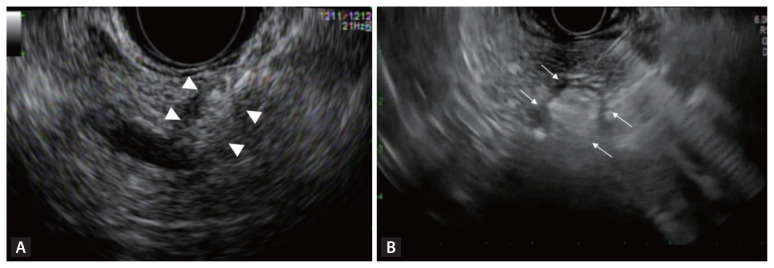

诊断技术的进步导致胰腺神经内分泌肿瘤(PNETs)的检测得到改善,从而增加了报告病例的数量。内镜超声(EUS)技术,包括与对比增强谐波成像的结合,有助于区分PNETs与其他肿瘤,而EUS引导的细针穿刺或活检提高了肿瘤的组织学诊断和分级。最近引入的eus引导下的乙醇注射或射频消融为PNETs的治疗提供了一种替代手术的方法。与手术比较显示出相似的结果,但副作用更少。尽管标准化的方案和长期随访的前瞻性研究仍然需要,但基于eus的方法是有希望的方法,可以有助于改善PNET患者的生活质量。

Advancements in diagnostic technology have led to the improved detection of pancreatic neuroendocrine tumors (PNETs) and thus to an increase in the number of reported cases. Endoscopic ultrasound (EUS) technology, including in combination with contrast-enhanced harmonic imaging, aids in distinguishing PNETs from other tumors, while EUS-guided fine-needle aspiration or biopsy has improved the histological diagnosis and grading of tumors. The recent introduction of EUS-guided ablation using ethanol injection or radiofrequency ablation has offered an alternative to surgery in the management of PNETs. Comparisons with surgery have shown similar outcomes but fewer adverse effects. Although standardized protocols and prospective studies with long-term follow-up are still needed, EUS-based methods are promising approaches that can contribute to a better quality of life for PNET patients.